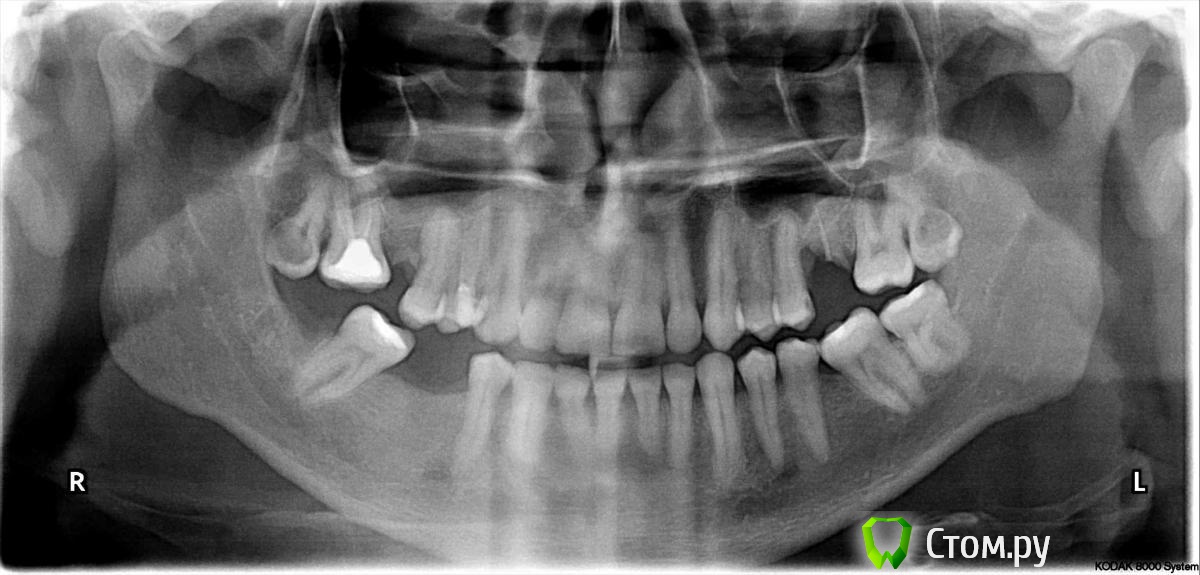

zepo Опубликовано 27 сентября, 2014 Поделиться Опубликовано 27 сентября, 2014 Добрый вечер!С зубами проблема, признаю запустил, не думал что все так серьезно.Решился и пошел в стоматологию, нижний правый зуб мудрости врач решила лечить, поставила пломбу, зуб начал болеть.Через 3-4 дня вскрыла, на следующий день решил его вырвать.Удаление сложное, три укола, стучали молотком, после того как отходил наркоз, страшная боль.На утро проснулся отека нет, боль стихла, сходил на проверку вроде все хорошо, но к ночи боль усилилась.На вид лунка отличная, отеков не было, но уже месяц, а боль не проходит.Чувство тяжести в челюсти, бывает стреляет в ухе.Конечно в течении трех недель боль утихла, раньше в течении двух недель пил кетанов через 4-5 часов, сейчас обхожусь одной в сутки.Но меня волнует продолжительная боль в челюсти и в ухе.Скажите это нормально? Также прикладываю снимок, прошу дать консультацию и что дальше делать? Ссылка на комментарий

red_butler Опубликовано 28 сентября, 2014 Поделиться Опубликовано 28 сентября, 2014 Удалите зуб мудрости на верхней челюсти Справа 1 Ссылка на комментарий

SDC Опубликовано 29 октября, 2014 Поделиться Опубликовано 29 октября, 2014 (изменено) Добрый день!Ходил к своему стоматологу, тот послал на МРТ, а после сказал показаться ЛОРу и невропатологу.Лор сказал что есть маленькая киста в левой пазухе, но боль у меня с правой стороны и отправила в невропатологу.Невропатолог поставил диагноз невралгия тройничного нерва, прописала уколы мильгамма и ксефокам, сегодня 4 день лучше не стало.Сам еще натираю камфорным маслом область возле уха, становится легче но под челюстью в районе лунки тяжесть и небольшая постоянная боль.При ходьбе в ухе постоянно слышен щелчек особенно поднимаясь по лестнице. Удалите зуб мудрости на верхней челюсти СправаИ слева Прежде всего исключить боли от верхних 8-х, с предположительным диагнозом пульпит. Повторная ренгенограмма зоны удаление 48з. - по ОПТГ подозрение на секвестр. Изменено 29 октября, 2014 пользователем SDC Ссылка на комментарий